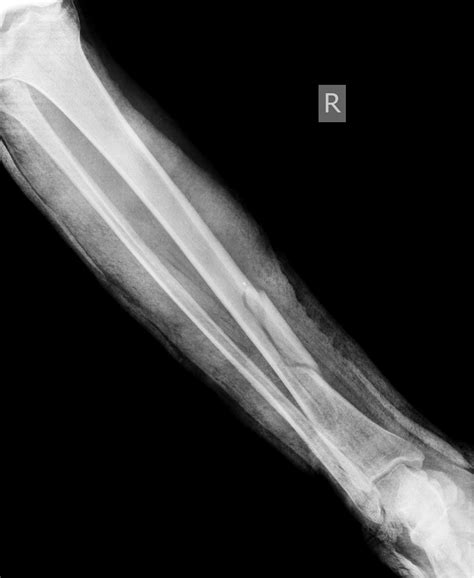

Is My Wrist Broken Or Sprained Infographic